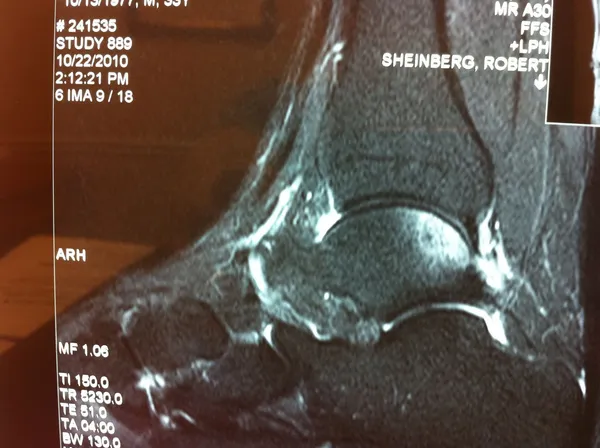

CT and MRI OCD Talus